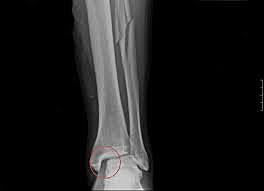

MY LEG BROKEN

In 2007 when I was 1 year old mi mom down the stair of my home and she slip in the last stair and squash mi leg againts the stair and my mom broke the fibula of my left leg.

And I were with the plaster in the nuresery school some months.